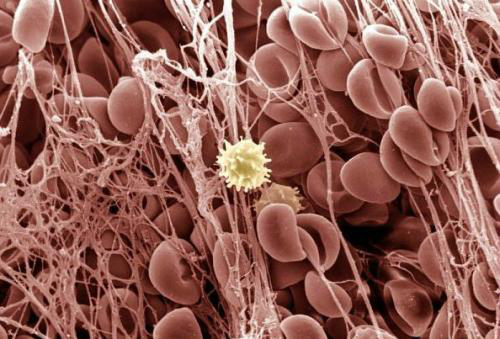

什么是血栓呢?简单地说,就是心脏和血管内血液凝结而成的血凝块。当我们的血管壁受到各种原因的损伤后,内膜下的胶原暴露于血液当中,激活了凝血系统,引起了血小板的聚集、黏附在受损的血管壁上,并吸引更多的血小板和白细胞聚集和黏附,和纤维蛋白一起形成珊瑚状的固体“骨架”。“骨架”间的血液变得缓慢甚至停滞,血小板、白细胞、红细胞凝集在一起,形成完整的血栓(图2)。

图2 电镜下形成血栓的纤维骨架和血细胞